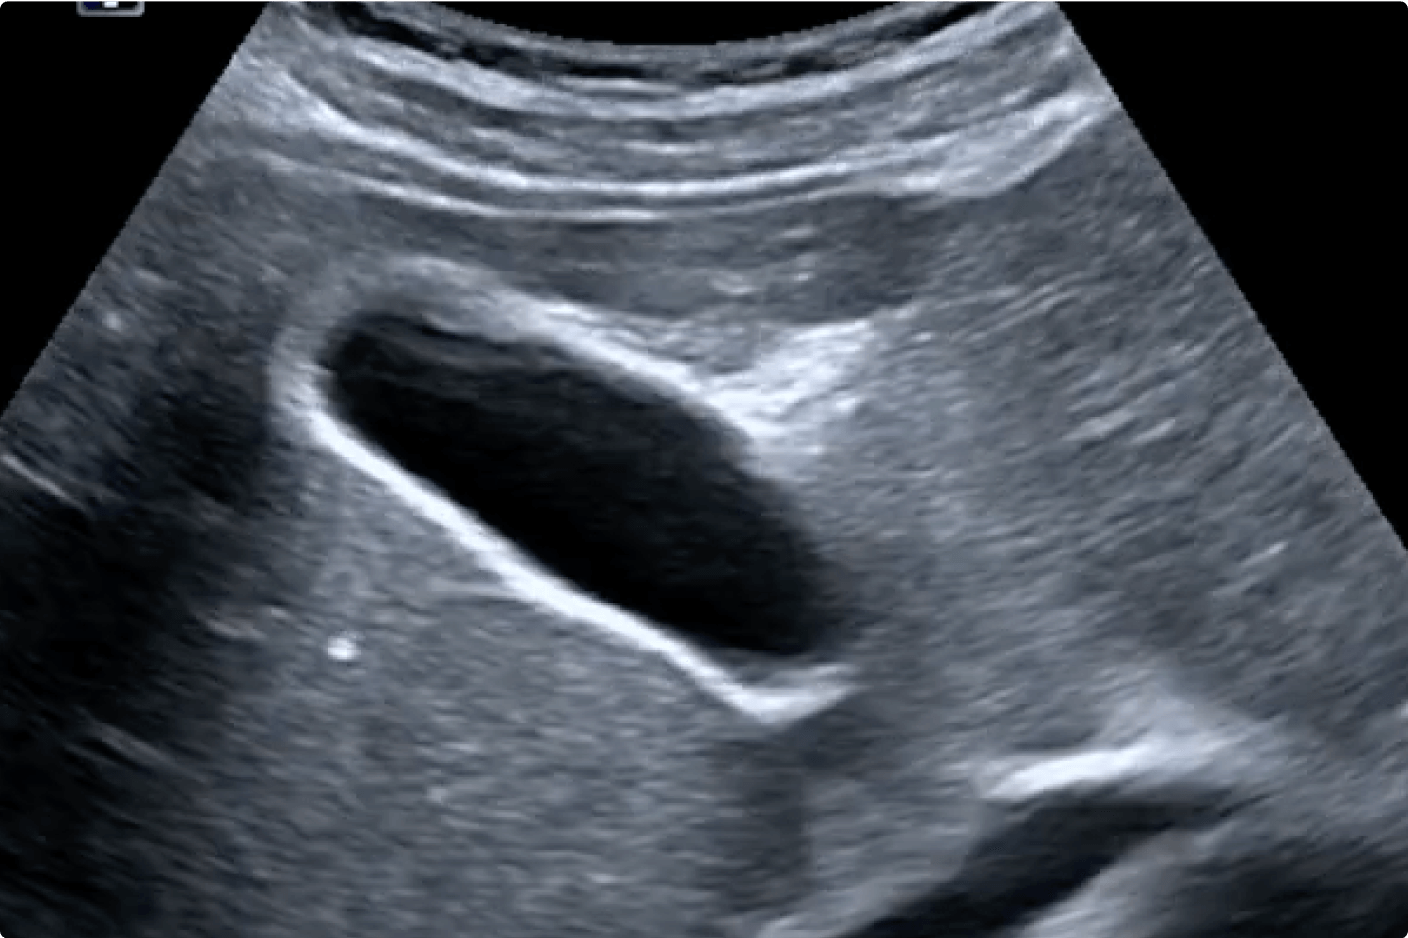

Flexibel und praxisnah zeigt dir in dieser Online-Fortbildung unser Experte Dr. med. Alexander Dittmann die wichtigsten Untersuchungstechniken und Befunde der Karotiden sowie der Vertebral- und Temporalarterien. Anhand realer Patientenfälle und Sonografiebilder aus der klinischen Praxis schulst du dein Auge und startest sicher in deine nächste Untersuchung.